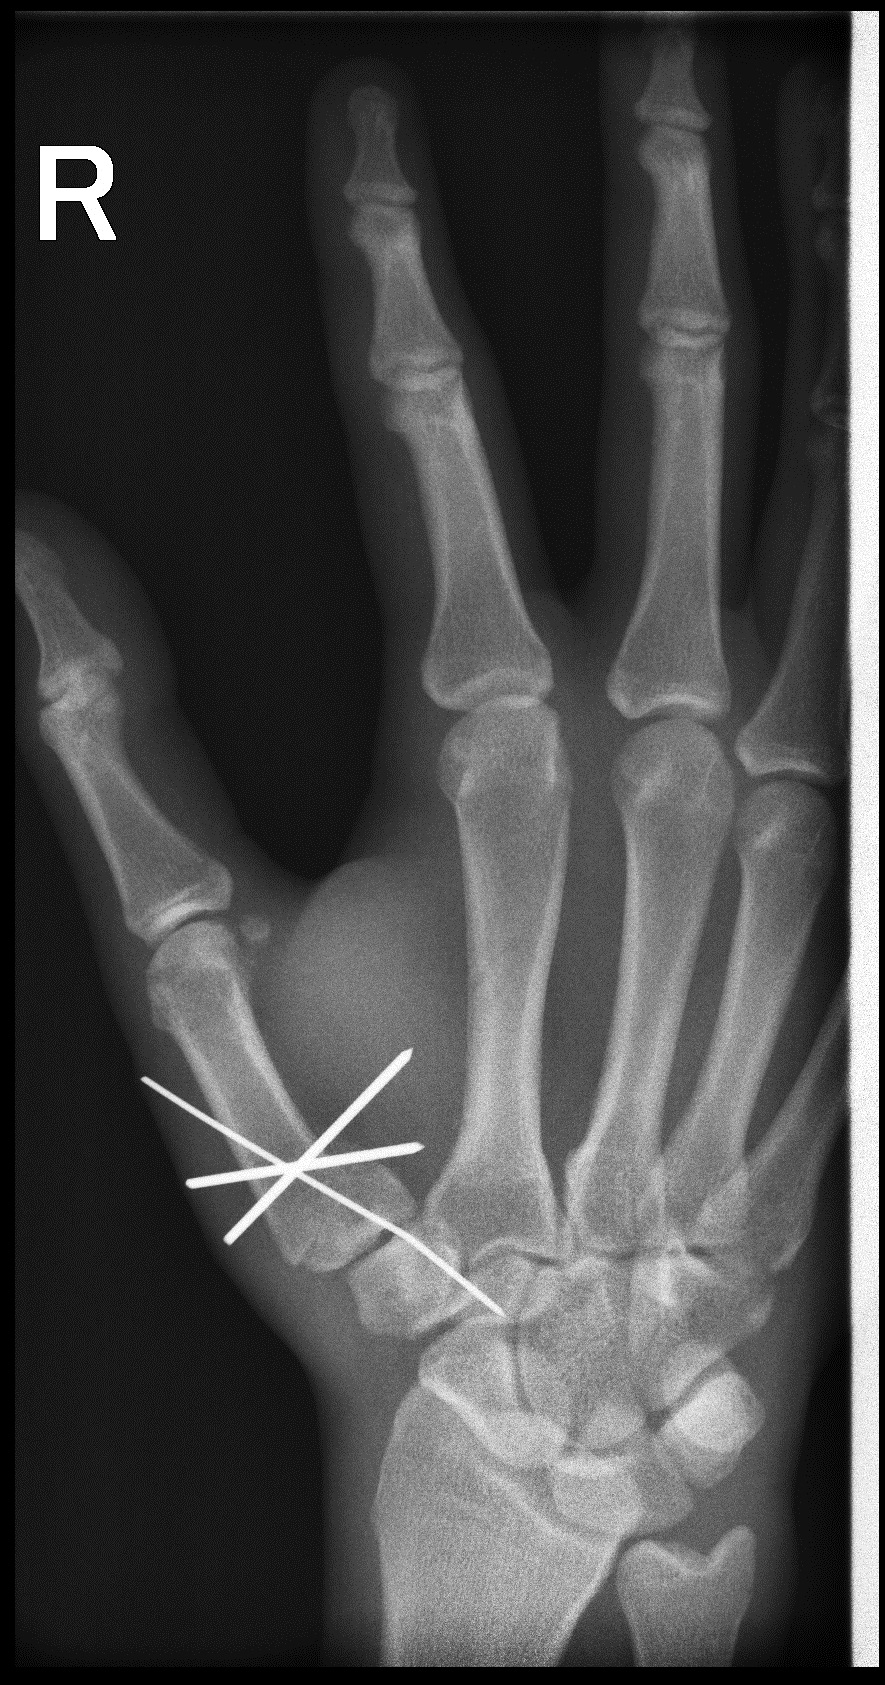

Утро травматолога

за 15 минут до конца дежурства:(

Такое адовое смещение, всего лишь от падения?!

играл в футбол и упал на отведенную руку

нет одну. два снимка